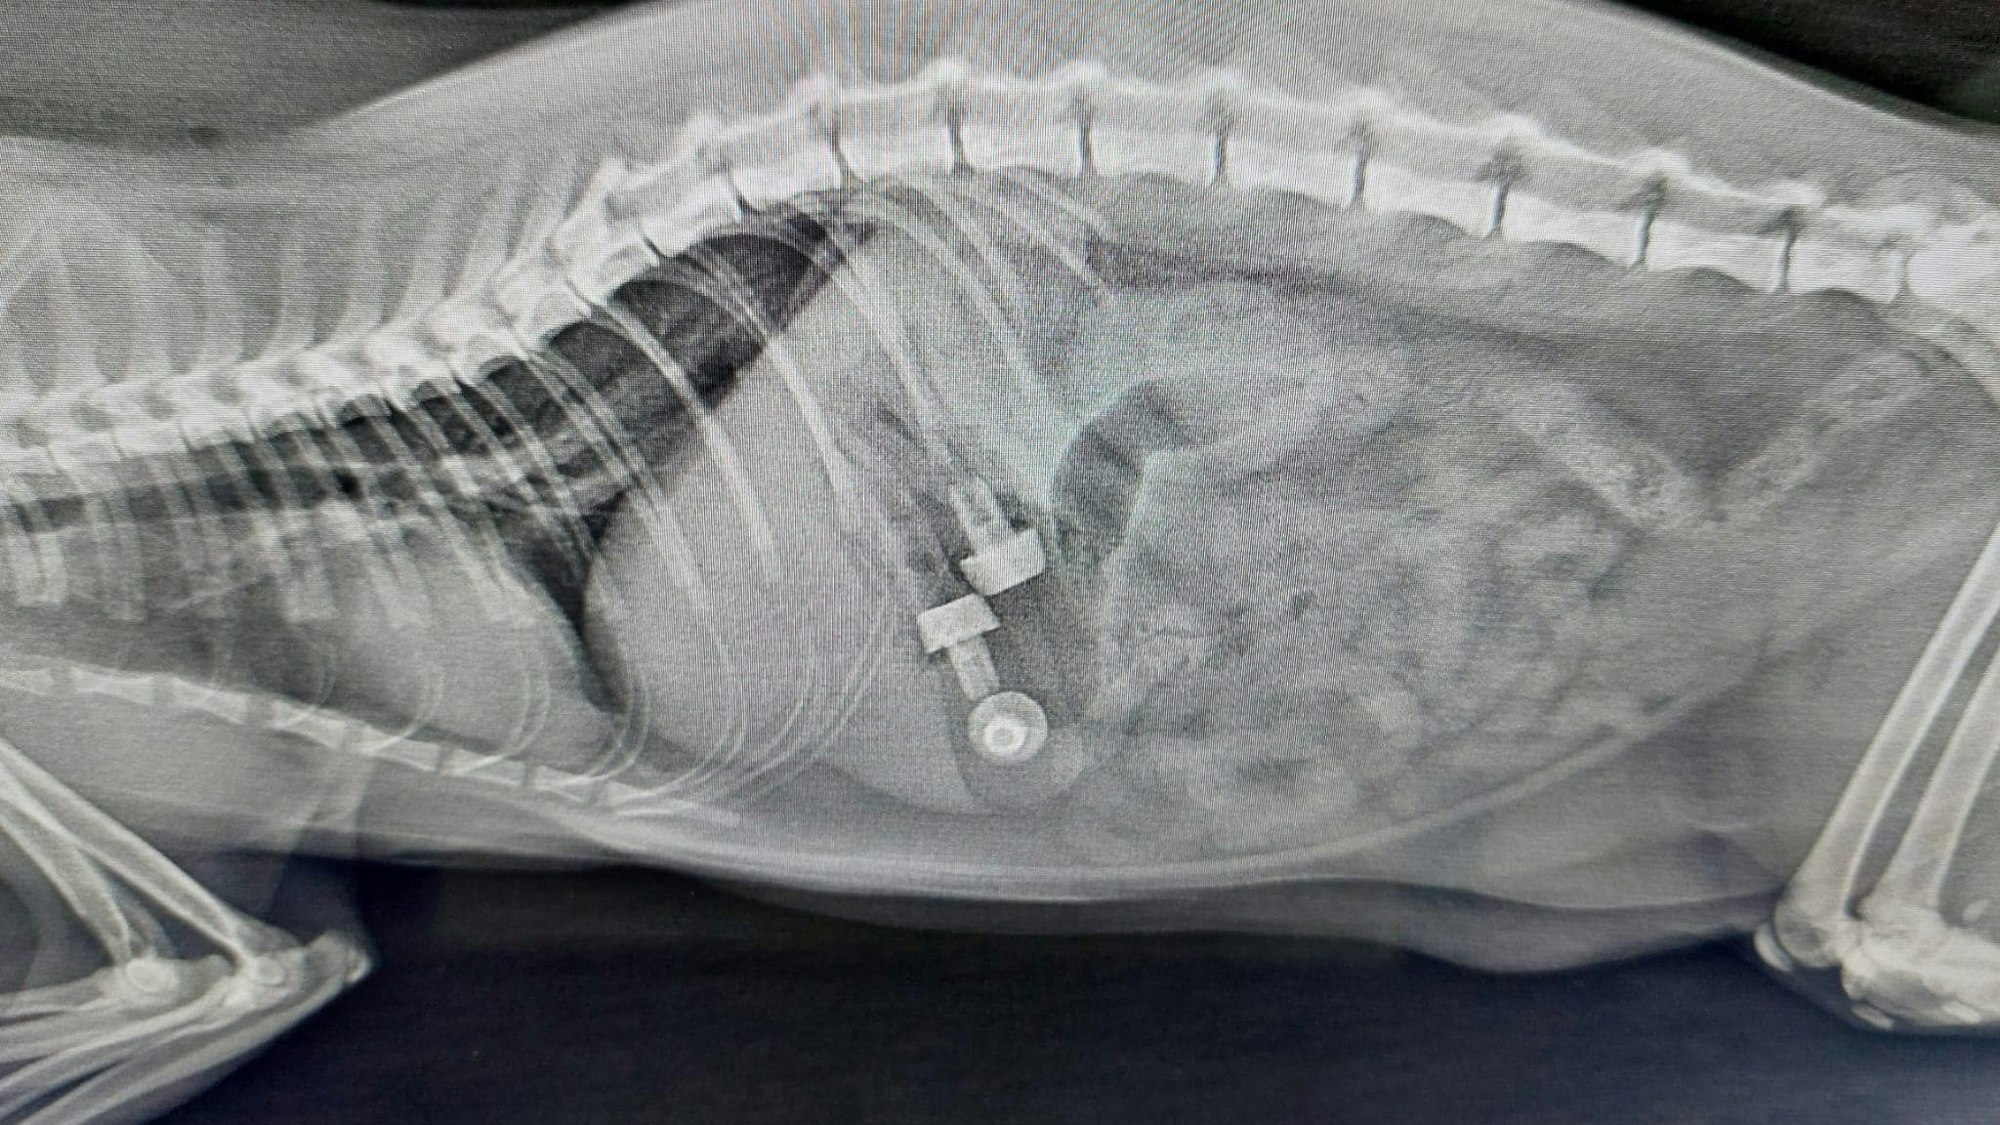

Was befindet sich da im Bauch von Kater Jack aus dem Tierheim Troisdorf? Das Foto ist vom 19. Oktober 2022.

Der Grund dafür: Drei recht große Fremdkörper hatten sich in Jacks Bauch verirrt, die erst durch ein Röntgenbild zum Vorschein gekommen waren. Nun mussten die Gegenstände operativ entfernt werden.

Aber was genau befand sich da eigentlich im Magen des Katers? Diese Fragen diskutieren zahlreiche Facebook-User unter dem Post des Tierheims, der das Röntgenbild zeigt (siehe oben).

„Sehen so aus wie die Plastikkorken von Sekt“, mutmaßt eine Nutzerin. Eine weitere Nutzerin hat eine andere Vermutung: „Das sind die Spitzen von Nerf-Pfeilen. Bei mir fliegen die dank meines Sohnes auch überall herum.“ Bei einer Nerf-Gun handelt es sich um Spielzeugwaffen, die mit Munition aus Kunst- oder Schaumstoff schießen.

Sektkorken oder Nerf-Gun-Munition? Was sehen Sie hier?

Gegenüber EXPRESS.de erklärte eine Mitarbeiterin des Troisdorfer Katzenhauses allerdings, dass es sich bei den herausoperierten Fremdkörpern um Plastikschrauben gehandelt habe.